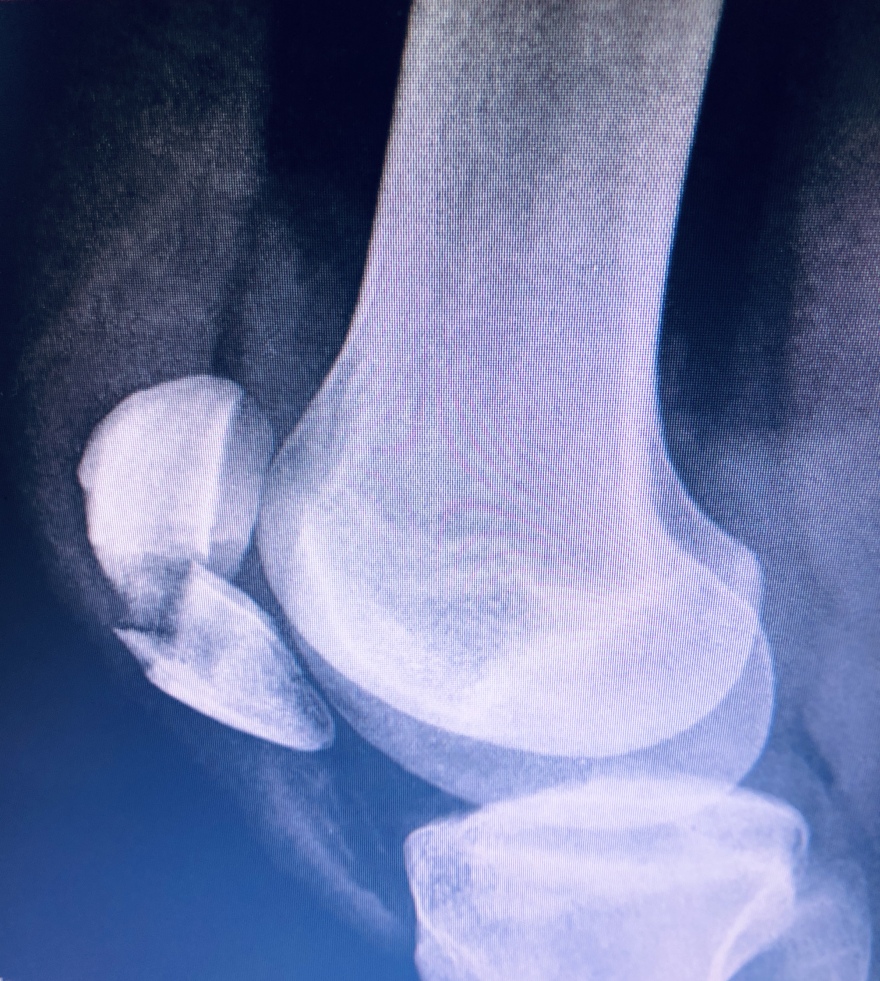

Παρακάτω φαίνεται το αποτελέσμα της έμβασης που είναι η αποκατάσταση του εκτατικού μηχανισμού του γόνατος , της αρθρικής επιφάνειας της επιγονατίδας και του χόνδρου που την καλύπτει , σημαντικοί παράμετροι για την σωστή και ανώδυνη λειτουργεία του γόνατος μελλοντικά.

Δείτε ακτινογραφίες μετά την επέμβαση: